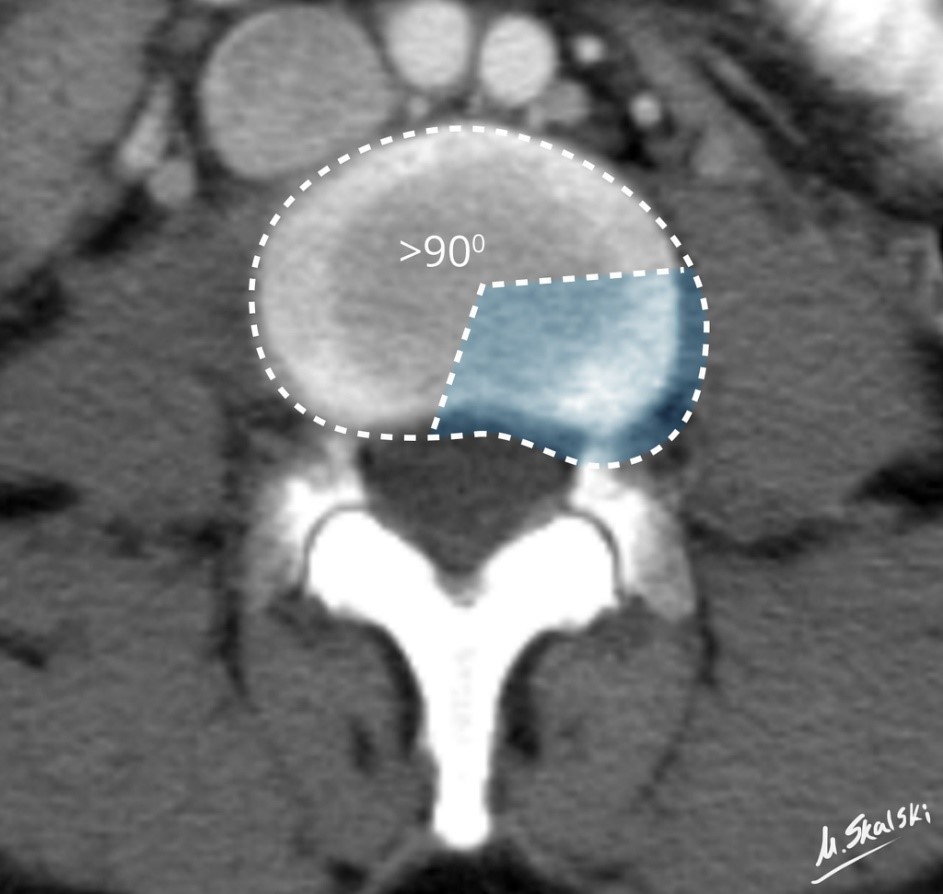

• Lumbal skiveprolaps – Del 1: Hva er prolaps?

Lumbal skiveprolaps – Del 1: Hva er prolaps?